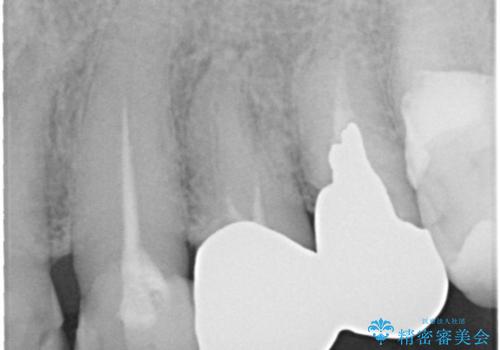

- 奥歯がなくて咬めないのと、全体的に見た目をよくしたいとのことで来院されました。

下顎の両側の奥歯が欠損しており、入れ歯をお持ちでしたが、うまく咬めずにほとんど使用していない状態でした。

上顎は全体的にクラウンの入れ替えと、下顎はインプラントの提案もしましたが、希望されなかったのでノンクラスプデンチャーの製作をする治療計画としました。

奥歯が欠損しており、上下の前歯が強く咬合する可能性があったので、上顎前歯の裏側は金属のものにしました。